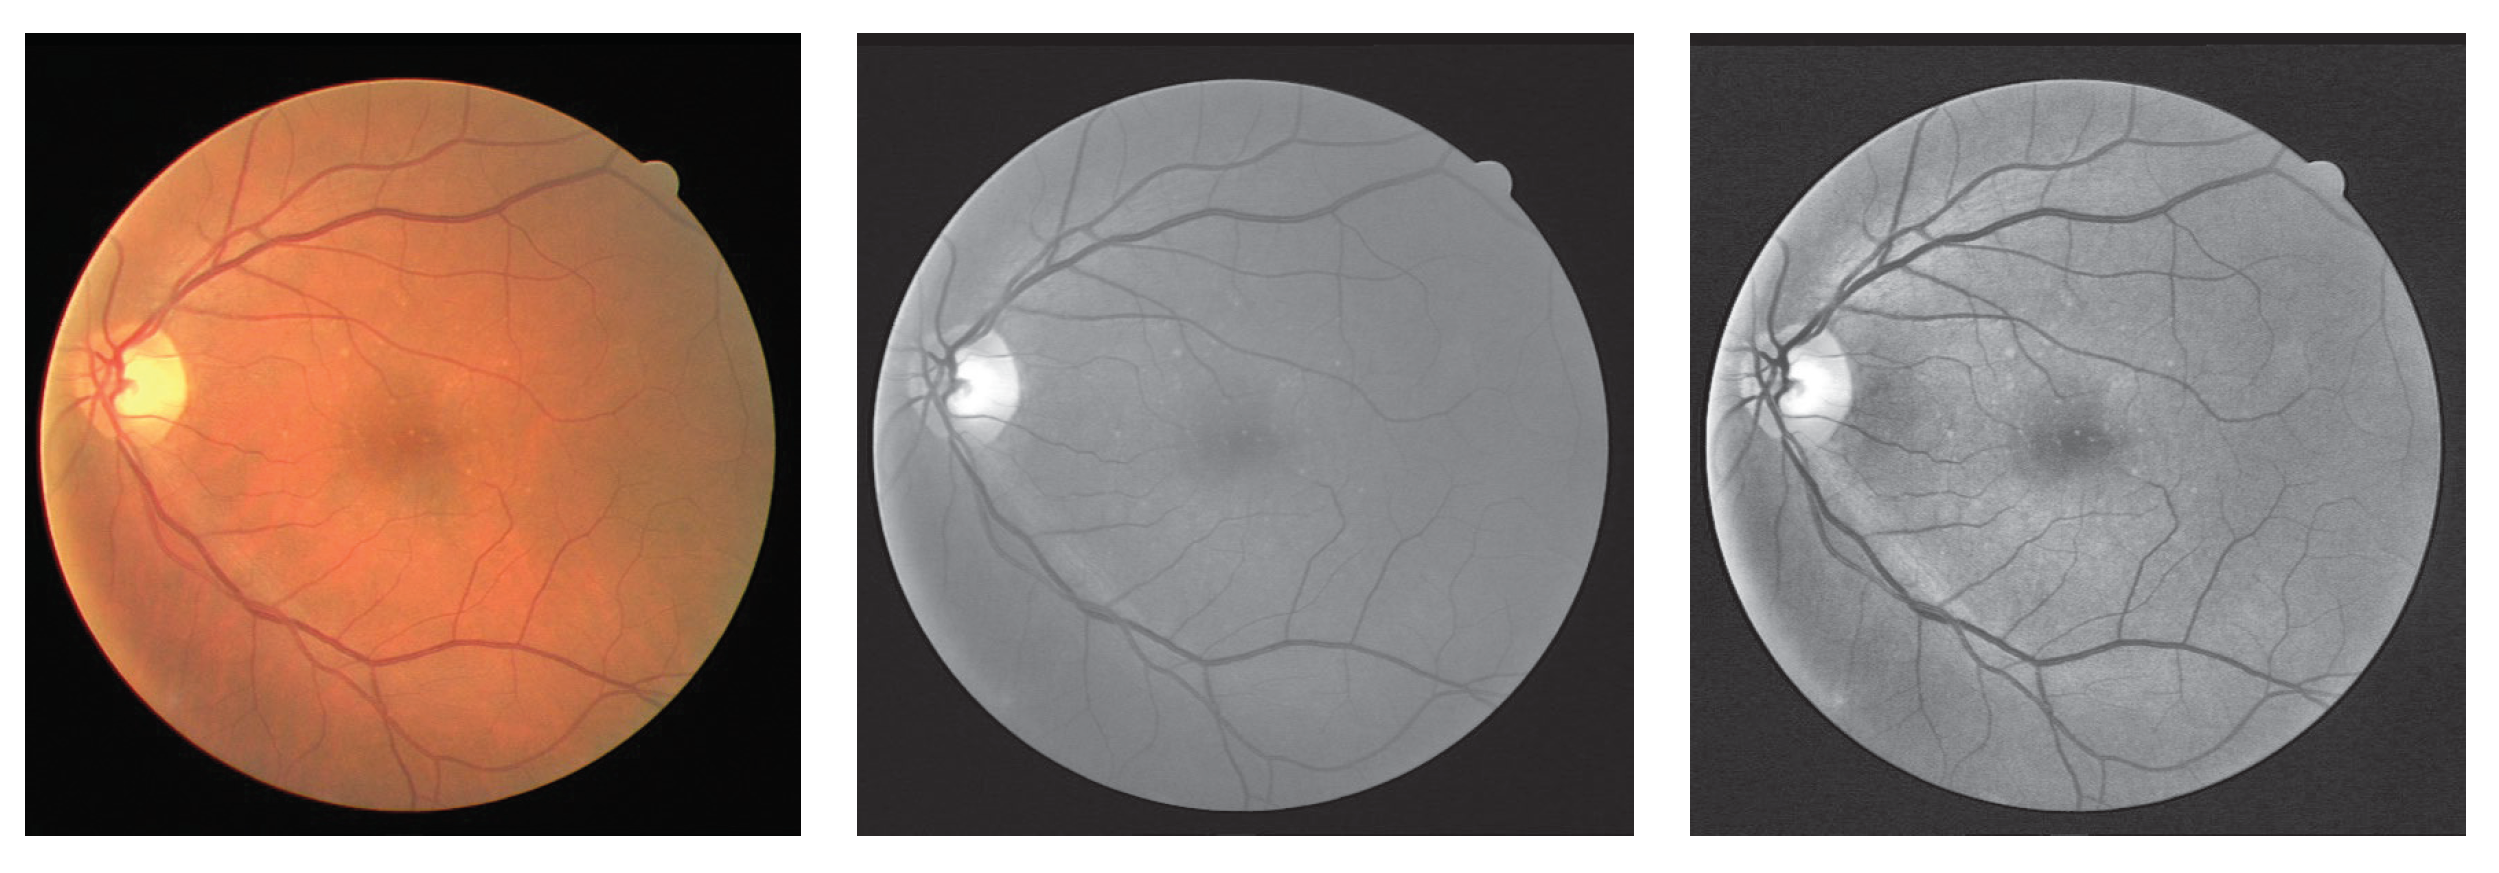

To validate the performance of the methods, we employ four public datasets for experiments. Figure 6 shows some samples from the datasets.

Before the training process, some augmentation methods are utilized to improve the amount of the training data and enhance the expression to alleviate the overfitting of the network. As a binary segmentation task, vessel segmentation needs more structural information about the vessel. Therefore, we utilize the single channel, the green channel of the original RGB image, to obtain the detailed vessel structure. Second, Contrast Limited Adaptive Histogram Equalization (CLAHE) [33] is employed to deal with the green channel to reduce the interference of color on blood vessel segmentation. The outputs of these operations are shown in Figure 7. For A/V classification, we use the original image to participate in the operation.

Figure 7. Results of preprocessing on the DRIVE dataset. The first column is the original image, the second column represents the green channel, and the last column shows the image processed by the CLAHE.